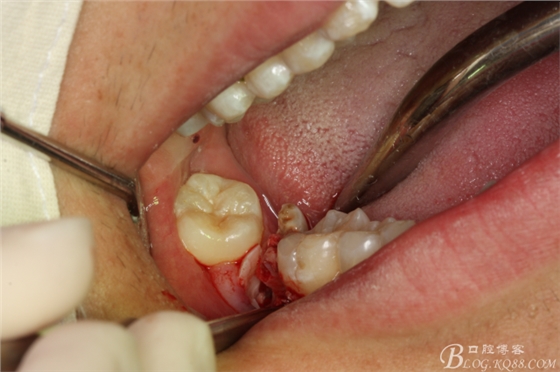

圖18.牙根取出后,牙槽窩形狀未改變

圖19.牙槽窩放膠質(zhì)銀止血海綿

圖20.金剛砂車(chē)針片切44牙冠、消除鄰牙阻力